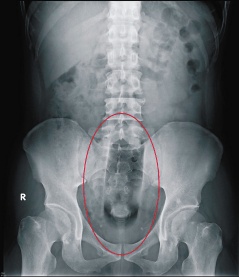

医师黄二荣表示,异物没入肛门就无法自行取出,从吴男的X光片显示,化妆水瓶已位在乙状结肠处,外壳硬滑,无法以常用的内视镜取出,加上痛苦扭动,当然无功而返。